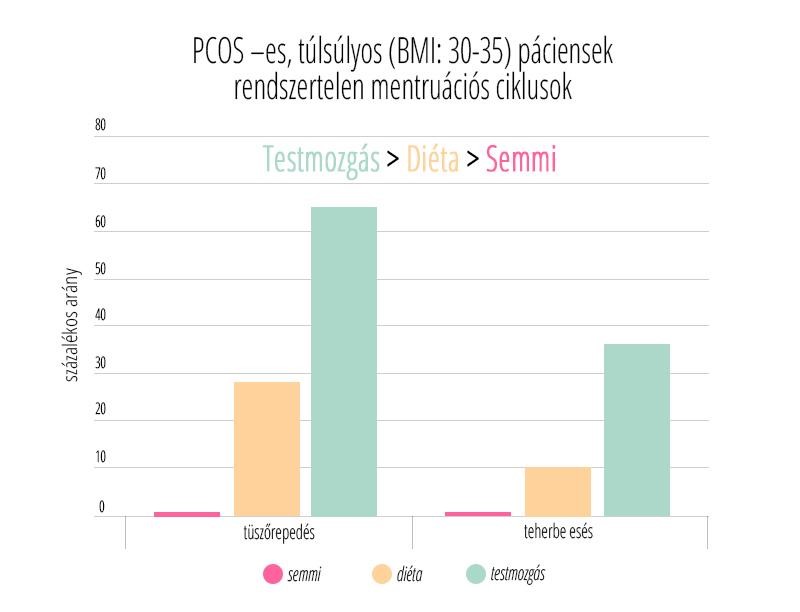

Az edukáció olyan fontos kérdéseket érint, mint: mi számít meddőségnek, mikor érdemes szakemberhez fordulni, hogyan hat az életkor a termékenységre, illetve milyen kockázatot jelentenek a szexuális úton terjedő fertőzések. Az iránymutatás külön kitér a legfontosabb kockázati tényezőkre, mint a dohányzás, a túlzott alkoholfogyasztás, az elhízás vagy éppen az alultápláltság, melyek mind kedvezőtlenül hathatnak a reproduktív egészségre. Ezzel szemben a kiegyensúlyozott, tápanyagokban gazdag étrend, a rendszeres testmozgás, valamint a dohányzás elhagyása bizonyítottan hozzájárulhat a termékenység megőrzéséhez és a későbbi problémák megelőzéséhez.